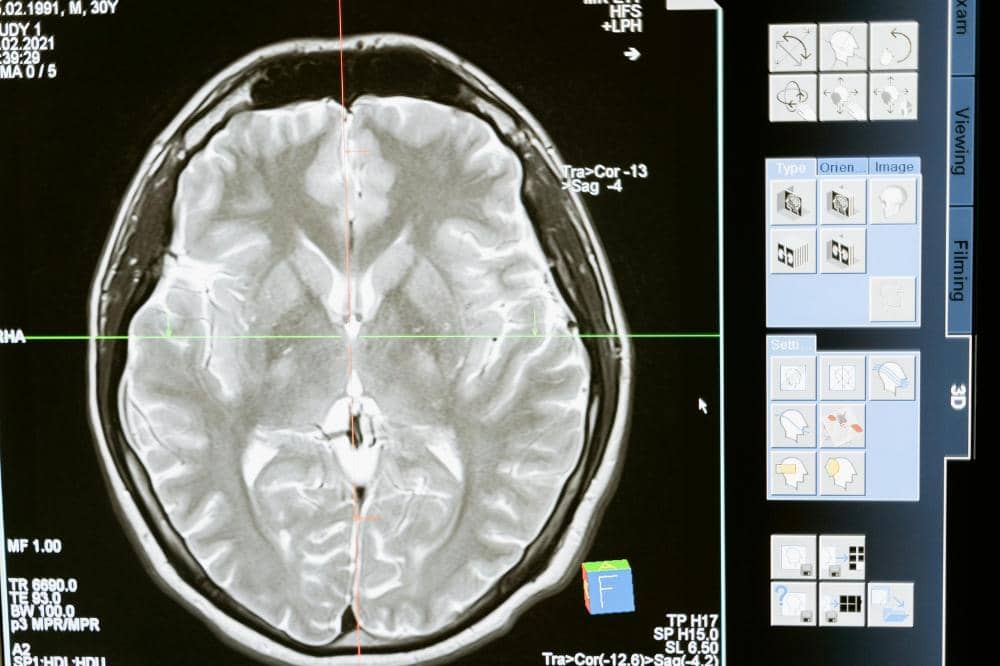

Pada usia remaja, otak anak sebenarnya sedang berada dalam masa transisi, terutama pada bagian yang mengatur kontrol emosi dan logika. Bagian otak yang merespons emosi dan ancaman berkembang lebih cepat daripada bagian yang berfungsi untuk berpikir jernih dan menahan diri.

Kondisi inilah yang membuat mereka sangat mudah merasa terpicu atau triggered oleh komentar atau situasi tertentu yang sebenarnya tidak bermaksud menyerang. Mereka merespons dunia dengan perasaan yang sangat intens karena emosi di otak mereka belum sepenuhnya bekerja dengan sempurna.